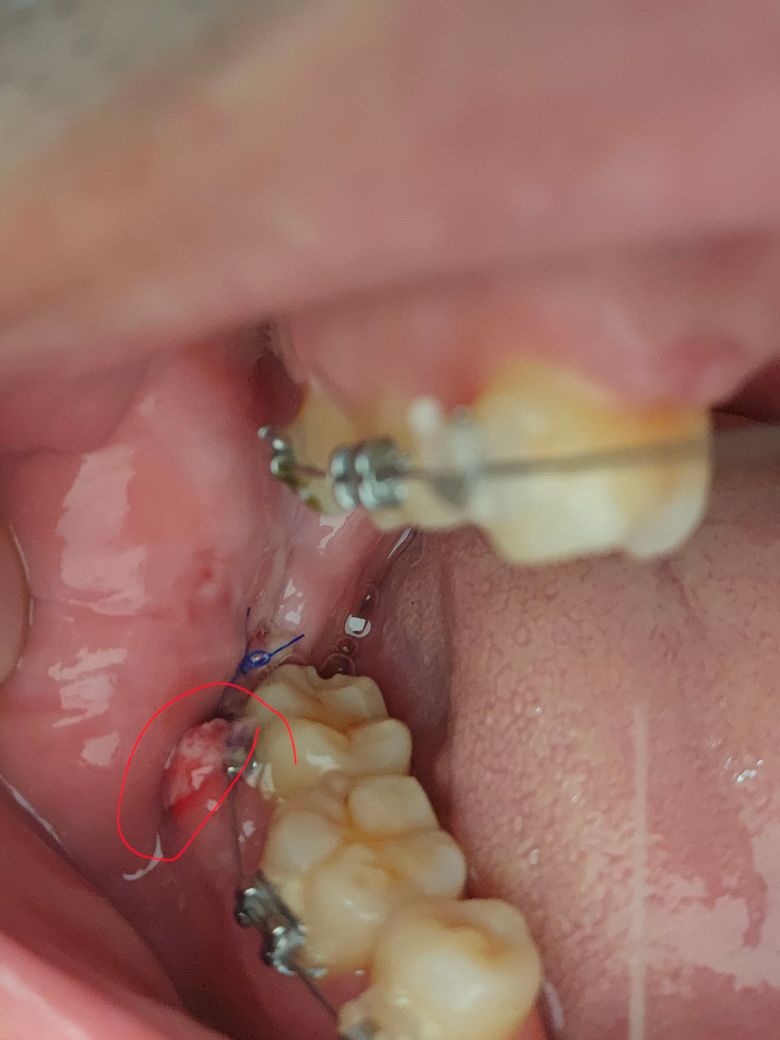

매복사랑니 발치 후 앞 어금니쪽 잇몸 붓고 변색됐어요

사랑니 앞쪽 잇몸이 엄청 붓고 맨 위에 빨간동그라미쪽은 하얀??색이 섞여서 부어올라있는데 발치한지 3일차입니다. 이상있는건가요?ㅠㅠ

• 1번 째 사진

발치후에 주변 잇몸도 자극을 받아 붓고 통증이 유발될수 있습니다. 현재 혈병이 형성되어 있는 것으로 보이며, 통증으로 불편감이 있는 경우 소염진통제 복용이 증상경감에 도움이 됩니다.